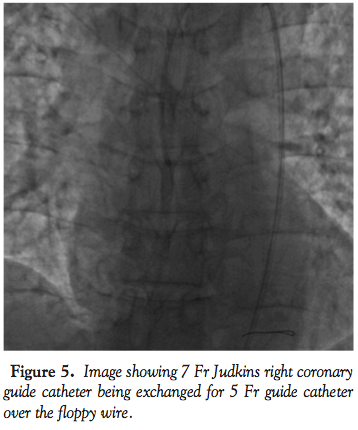

Another 0.014-inch choice floppy wire (Boston Scientific) was passed across the lesion. The 7 Fr guide catheter was withdrawn and a 5 Fr guide catheter was passed over the choice floppy wire (Figure 2), which was slowly intubated deep into the mid segment of the RCA (Figure 3). The choice floppy wire was then withdrawn while the stabilizer plus wire was kept in the artery. The hub of the guide catheter was disconnected from the Y-connector and a 20 mL Luer-Lok syringe (Becton-Dickinson) was attached. Maintaining a constant and moderate

negative suction, the guide catheter was slowly withdrawn from the artery and out of the femoral sheath. Flushing of the guide catheter revealed chunks of intact thrombus that matched the filling defect (Figure 4). While all this was done, the stabilizer wire was in the RCA to ensure access to the distal RCA. There was significant improvement in blood pressure of the patient along with relief in the chest pain. A 7 Fr guide catheter was passed over the stabilizer wire and the RCA was engaged (Figure 5). Angiogram revealed a widely patent artery with TIMI III flow and a residual stenosis of 80% in mid segment of the RCA (Figure 6). The lesion was stented with a non-drug-eluting Prokinetic stent 4 mm x18 mm (Biotronik AG). Post-dilatation, patient developed slow flow, which was successfully managed. Final angiogram showed a well-expanded stent with TIMI III flow (Figure 7). Post-procedure hospital course of the patient was uncomplicated and he was discharged on dual antiplatelet regimen on day 4.